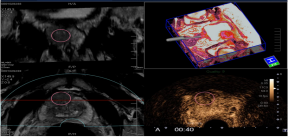

4.智能传感器3D成像(Smart Sensor 3D) :该技术在于弥补常规容积探头成像范围的不足,容积图像范围更大。Smart Sensor 3D可以与其他成像技术联用,包括超微血流成像iSMI、超声造影CHI,Fly Thru,剪切波弹性成像SWE等,

5. 仿内镜导航技术Fly Thru:实时动态显示人体内液性的管腔、体腔和血管内部的立体结构,帮助临床对体内的微小病变更好的发现和治疗,应用于容积探头或Smart Sensor 3D模式。